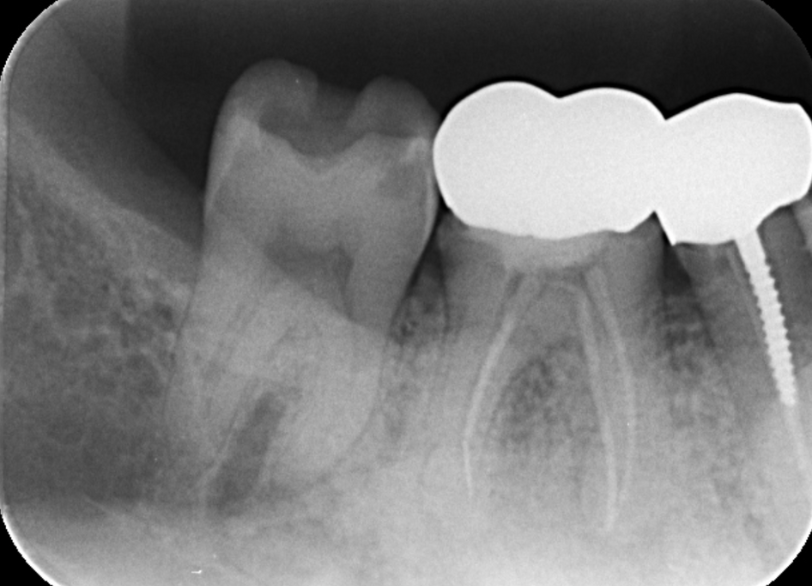

①失活による根管治療を行った

②術前CTによる根尖部の未治療および根尖透過像

| 診断 | 右下6.7根尖性歯周炎 | ||||

| 処置内容 (または主訴) | マイクロスコープ治療を用いた感染根管治療 | ||||